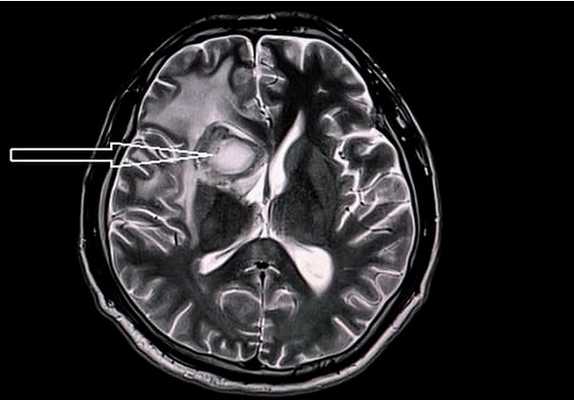

Очаг ишемии и некроза головного мозга (показан стрелками) на МРТ

Интракраниальное кровоизлияние на МРТ (стрелка указывает на гематому)